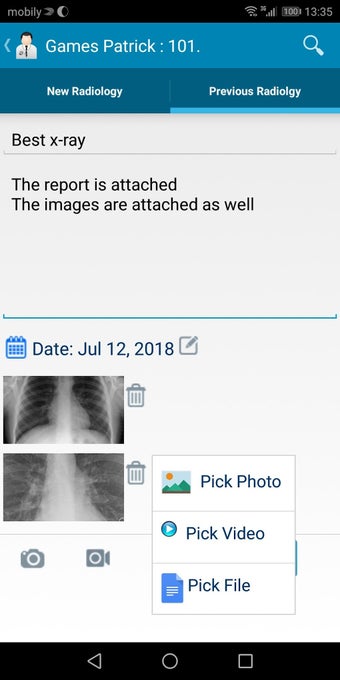

The Android Medical Records App by MedClin is a free medical records tracker app that allows users to store anamnesis, patient records, patient history, and health information. It is easy to use and provides numerous features such as username and password authentication, exporting medical data to Excel Sheet, and the ability to attach medical documents of any type. The app also has a smart search feature that allows users to search for patient information by name or ID, and even capture a photo for their profile.